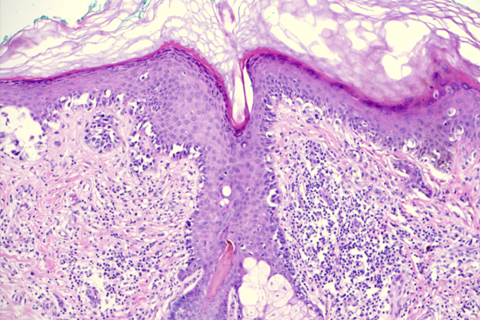

The dermatopathology service handles more than 8,000 skin biopsies annually, encompassing a wide variety of neoplastic and inflammatory conditions. Biopsies primarily come from outpatient offices. There is a robust number of resections for melanoma and cutaneous soft tissue tumors, as well as sentinel lymph node biopsies for melanoma and Merkel cell carcinoma. These typically come from inpatient operating rooms. Resections of other organs (liver, lung, intestine) that contain metastases of cutaneous malignancies are also handled by the dermatopathology service.

While most cases are evaluated based on H&E morphologic findings, a full range of diagnostic modalities is employed, including histochemical stains, immunohistochemistry, direct immunofluorescence, fluorescence in situ hybridization, and molecular techniques such as polymerase chain reaction.